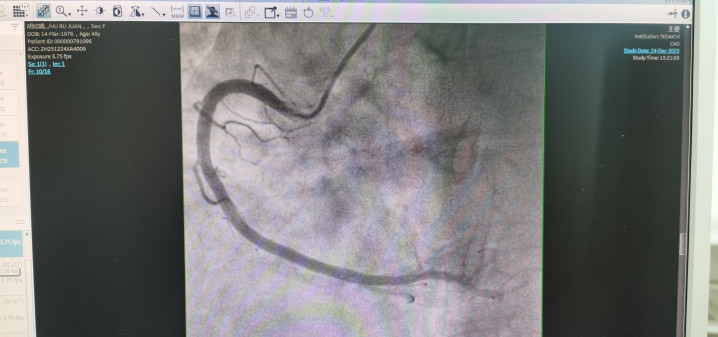

冠状动脉造影